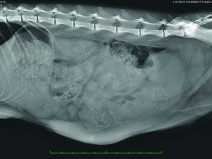

• Échographie de la rate, des surrénales et des noeuds lymphatiques / TP ponctions échoguidées

Public visé : La formation est ouverte aux docteurs vétérinaires qui souhaitent offrir au sein des établissements de soin vétérinaire des prestations de qualité accrue en échographie des animaux de compagnie

Prérequis : Être docteur vétérinaire. évoluer dans une structure de soins vétérinaires disposant d’un échographe ou vouée à en disposer dans un...

Du 21 au 22 octobre 2017

Mérignac (33700)

Imagerie Médicale

G.E.I.M.

217